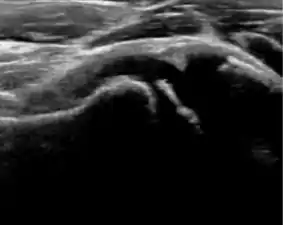

During childhood, ultrasound is a quick method to assess hip pain and quite often may be used to avoid use of irradiating techniques, such as radiography or CT. Ultrasound allows evaluation of joint effusion, synovial thickening and neovascularity, the bone/cartilage contour, and the femoral head-neck alignment. Although sonography is extremely sensitive in detecting increased synovial fluid, it is nonspecific and cannot be used with accuracy to determine the type of fluid. Transient synovitis of the hip, despite being the most frequent cause of pain in children between 3 and 10 years, remains a diagnosis of exclusion. It usually shows anechoic fluid, but echogenic fluid can also be found. The effusion is considered pathologic when it is measured at >2 mm in thickness. The differential diagnosis is wide, including osteomyelitis, septic arthritis, primary or metastatic lesions, LCPD, and SCFE. Discrimination from septic arthritis is challenging, often requiring joint aspiration. In septic arthritis, US is able to demonstrate a hip joint effusion, synovial thickening, and cartilage damage, although the appearances are nonspecific.[1]

Figure 12:

Normal ultrasound appearance of the femoral head-neck junction.

Joint effusion in transient synovitis of the hip.

Flattening of the femoral head in a patient with Perthes disease.

Step in the femoral head-neck junction in a patient with SCFE.